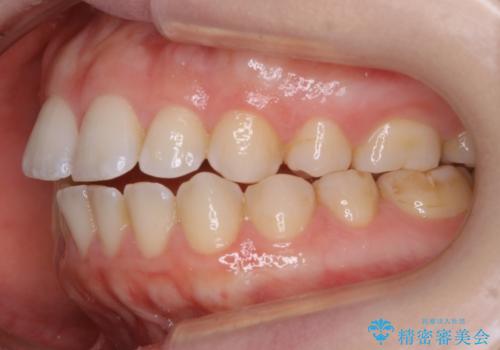

【非抜歯】上下の前歯が噛み合わないオープンバイトの治療

- 噛み合わせの不調を主訴にご来院されました。

骨格的な問題もあり、噛んだ時に奥歯しか当たらず前歯の被蓋があまりない状態でした。

奥歯を沈めて噛み込みを深くしていくことで被害の改善が起こるとともに、下顎自体が前上方に回転移動することで顔貌的にも変化を出すことができます。

臼歯の位置が高く噛んだ時に奥歯しか当たらなかったり、舌癖などが原因で前歯が前に倒れてしまうことで上下の前歯の被蓋がなくなってしまっている状態をオープンバイトといいます。

前者の場合は臼歯を圧下し沈めてあげることで改善させます。後者の場合は前方に傾斜している歯を元の角度に戻してあげることで改善しますが、舌癖がある場合はその癖自体を無くす治療をしない限りまた同じ状態へと後戻りしてしまいます。